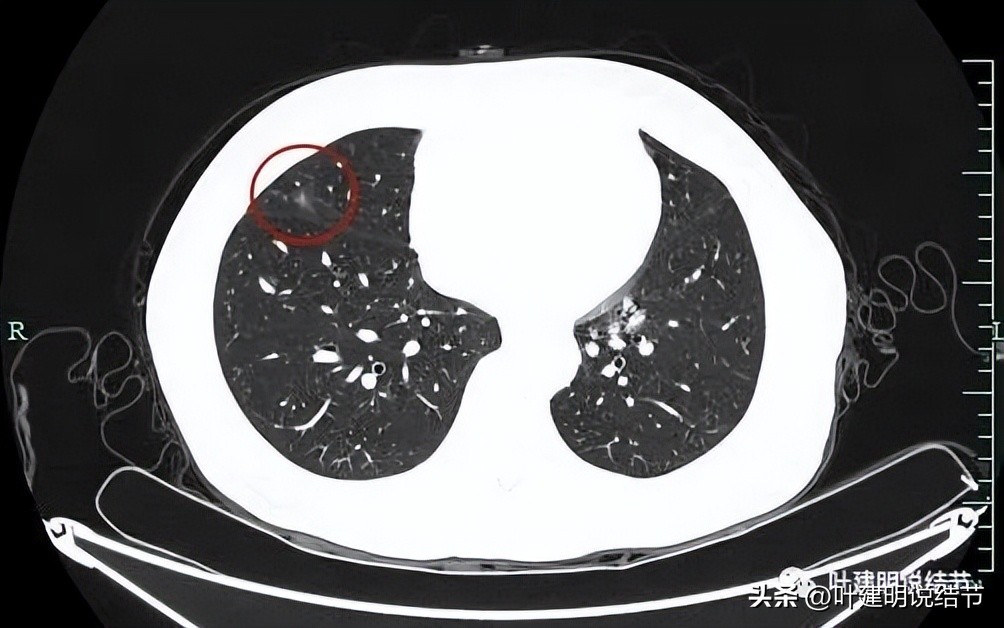

再看左下叶的主病灶,此层见其是磨玻璃密度,轮廓较清,内部密度欠均匀。

有明显血管征,血管进入后有分支发出,病灶表面显得有毛刺样。

病灶中间有空腔。